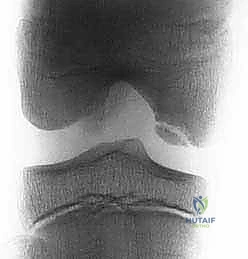

Radiographic Evaluation

A standard radiographic knee evaluation is our first step:

* Standing Anteroposterior (AP) views in full extension: To identify angular changes and compare joint space height.

* 45-degree Flexion Posteroanterior (PA) weight-bearing view: Crucial for identifying subtle joint space narrowing, which can be missed on full extension views.

* Non–weight-bearing Lateral view (45-degree flexion): With posterior femoral condyles overlapping, this view helps assess the posterior aspects of the condyles.

* Axial view of both patellae: Essential for evaluating patellar alignment and trochlear morphology.

* AP knee flexion view: Excellent for outlining the femoral intercondylar notch and best demonstrating osteochondritis dissecans lesions, particularly those in the lateral aspect of the medial femoral condyle.

* Long-leg hip-to-ankle films: Accurately determine varus or valgus alignment, which is critical for assessing overall limb mechanics and ruling out significant angular changes that contraindicate autografting.